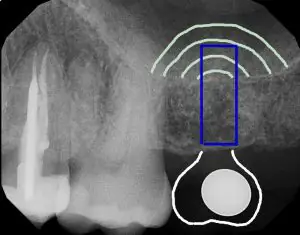

Main Content Abstract A minimally invasive technique, osseodensification, can be used to facilitate maxillary sinus bone graft augmentation for placement of dental implants. The crestal